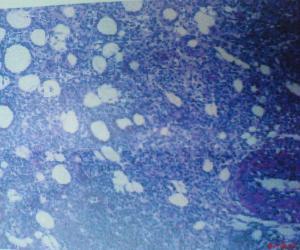

皮下脂膜炎性T細胞淋巴瘤此瘤的診斷主要靠活組織病理檢查。最有助於診斷的特點為:結合細胞不典型和病變的結構方式。常需數次活組織檢查,在隨後標本中瘤細胞不典型性變得較明顯時即可確診。需與下列疾病鑑別:

①組織細胞吞噬性脂膜炎:1980年首先報告,現多認為與此瘤為同一疾病;

②良性反應性脂膜炎(包括結節性紅斑、硬紅斑):無不典型淋巴樣細胞;

③原發性CD30+大細胞淋巴瘤:患者雙峰年齡分布,高峰為20~30歲和60~70歲,皮膚結節較淺,呈紅或紫色,可破潰,偶或自行消退。常累及淋

皮下脂膜炎性T細胞淋巴瘤巴結,細胞浸潤常集中於真皮,而累及皮下組織較不明顯。瘤細胞主要為大淋巴細胞,有些為多核,胞核往往排列成環狀,核仁常明顯,胞質豐富;

④多形T細胞淋巴瘤,中等大和大細胞型:見於老年人,不伴噬血細胞綜合徵。瘤細胞主要在真皮。胞核明顯不規則、深染,有不同程度明顯的核仁,胞質常透明或淡染;

⑤血管中心性免疫增殖性損害:此概念由Jaffe1985年提出,包括鼻部和鼻型自然殺傷細胞(NK/T)T細胞淋巴瘤(NNK/TL)、淋巴瘤樣肉芽腫病等,病變特徵為血管中心性和破壞性不典型淋巴樣細胞浸潤,常見廣泛壞死和核碎裂。NNK/TL與EB病毒(EBV)相關。NK/TL不典型細胞無克隆性TCR基因重排,CD56+,而本病的瘤細胞示克隆性TCR基因重排,與EBV無關。